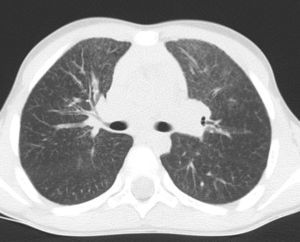

At the age of 30 months (when the last episode had occurred 2 months previously), a chest X-ray was obtained during a stable period of good health in the twin with the more severe clinical history, and persistent interstitial-alveolar involvement was observed; a high resolution CT scan (HRCT) revealed ground-glass opacification of the image, with an interstitial pattern and fine nodules (Fig. 1).